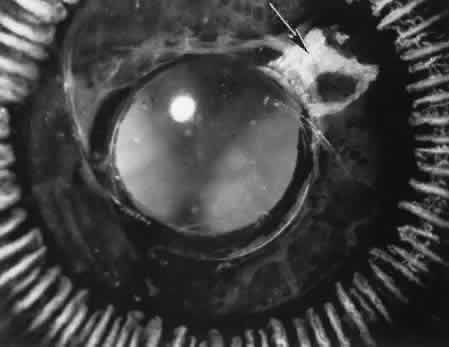

Fig. 25. The ciliary processes (arrow) in a wound placed too far posteriorly in an attempted iridencleisis (a type of glaucoma procedure). Persistent flat anterior chamber followed the formation of peripheral anterior synechiae (inset), producing secondary closed-angle glaucoma. The globe was subsequently enucleated. (Hematoxylin-eosin stain; × 28.)

Fig. 26. Complications related to a limbal wound. A. The posterior edges of the limbal wound are poorly apposed. Incarcerated vitreous can be identified in the wound at higher magnification, (inset). The cut edges of Descemet's membrane are widely displaced (d). (Hematoxylin-eosin stain; A, × 54; inset, × 101.) B. Vitreous is incarcerated into the wound immediately anterior to an area of total anterior synechiae. C. At higher magnification, vitreous can be clearly identified in the wound. A fibrous membrane is present posterior to Descemet's membrane. The arrows indicate the cut edges of Descemet's membrane. (Periodic acid/Schiff stain; B, × 16; C, × 40.)